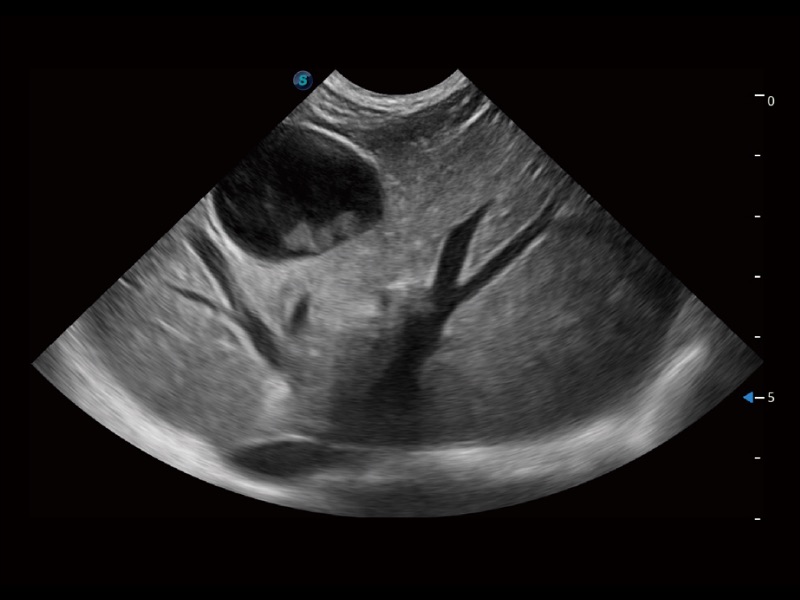

ProPet 70 进一步提升了微米成像算法,更加注重对基础原始图像的还原和保留,在有效减少斑点噪声、增强组织边界显示的同时,避免过度优化丟失真实的解剖信息。

增强穿刺针在动物解剖结构中的位置,提高穿刺介入的安全性和准确性。

操作简便,无需高频度外力作用即可真实反映组织的形变,快速评估肿瘤良恶性。